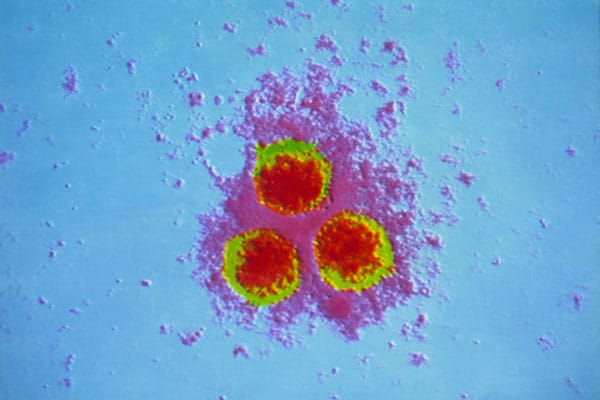

Медицинские снимки и изображения опоясывающего герпес вируса

Раздел: Фотодневник открытий